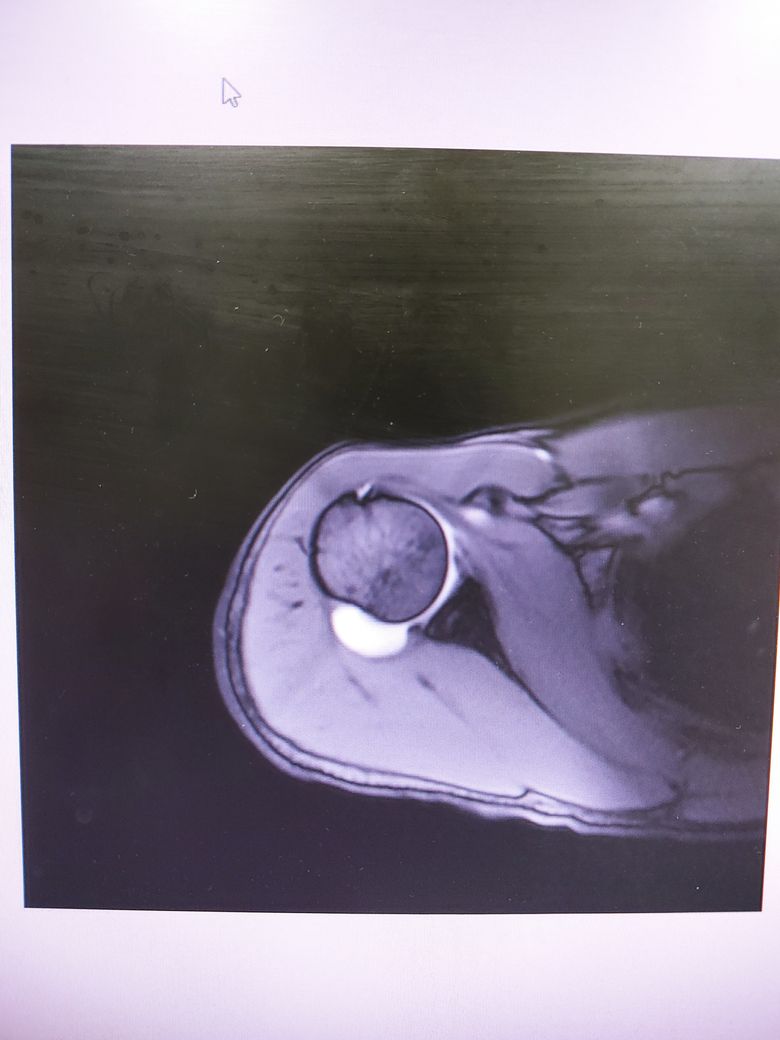

방카르트인지 한번 봐주시겠어요?

어깨를 움직일때 뒤쪽에 깊숙한 통증이있습니다.

염증인거 같긴한데 와순파열은 아닐지 걱정됩니다.

다음 사진에서 방카르트 소견이 있는 건지 봐주실 수 있을까요

• 3번 째 사진

MRI 4컷만 가지고는 방카트 병변을 명확하게 진단하기 어렵습니다.

현재 사진만으로는 방카트로 보이지는 않습니다.